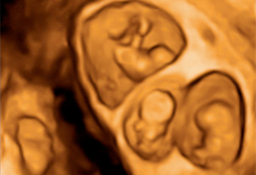

Ecografía de la semana 12

Confirma la edad gestacional y el número de bebés

Los motivos por los que los ginecólogos recomiendan realizar una ecografía en la semana 12 de embarazo tienen que ver con el desarrollo anatómico y el tamaño del feto: ahora es lo bastante grande para comprobar si presenta anomalías. Además, ya se puede ver con claridad si hay uno o dos (o tres) bebés, calcular  la fecha probable de parto teniendo en cuenta la edad gestacional, y confirmar que esta coincide con el desarrollo del bebé. Se puede medir el llamado pliegue nucal (si sobrepasa unos parámetros a veces es indicio de problemas cromosómicos) y, si el bebé se deja, conocer su sexo.